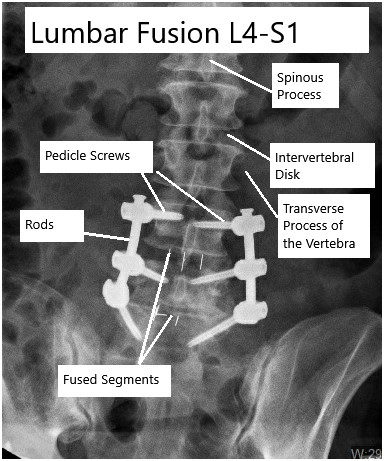

Spinal fusion Mayo Clinic

Posterior Lumbar Fusion Surgery DePuy Synthes

Lumbar Fusion Neurosurgery of St. Louis STL Brain Spine Doctors

Spinal Fusion OrthoInfo AAOS